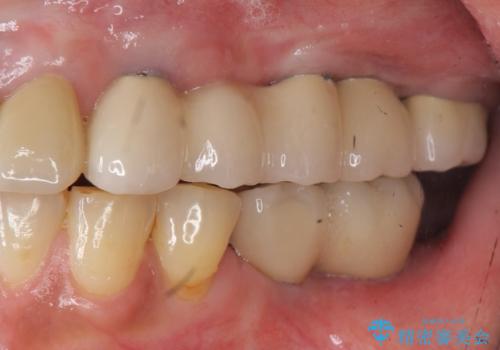

痛くて噛めない インプラントで全て治療したい

- 痛くて噛めない、これまでだましだまし治療をしてきたがこれを機にすべてきっちりと治したい、口の中の悩みを解決したいと来院されました。

抜歯や歯周病治療、欠損補綴を含め、全顎的な治療を計画・提案します。

口腔内に歯の破折や歯周病、虫歯、欠損など複数の問題が存在する場合局所的に問題を解決していくのではなく全顎的な治療を行っていくことで長期的な予後を見込むことができます。